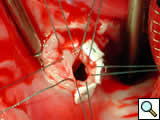

In Figure 10, the surgeon has insufflated the right ventricle with cold saline; the tricuspid valve is seen to be competent. There is no saline coming out of the Gerbode defect, indicating no communication between the right ventricle and the anatomic channel between the left ventricle and the right atrium. There is only a small amount of blood coming out of the Gerbode defect (green circle).

Figure 11 shows the placement of 5 pledget-supported Ticron sutures around the circumference of the ventriculo-atrial defect.